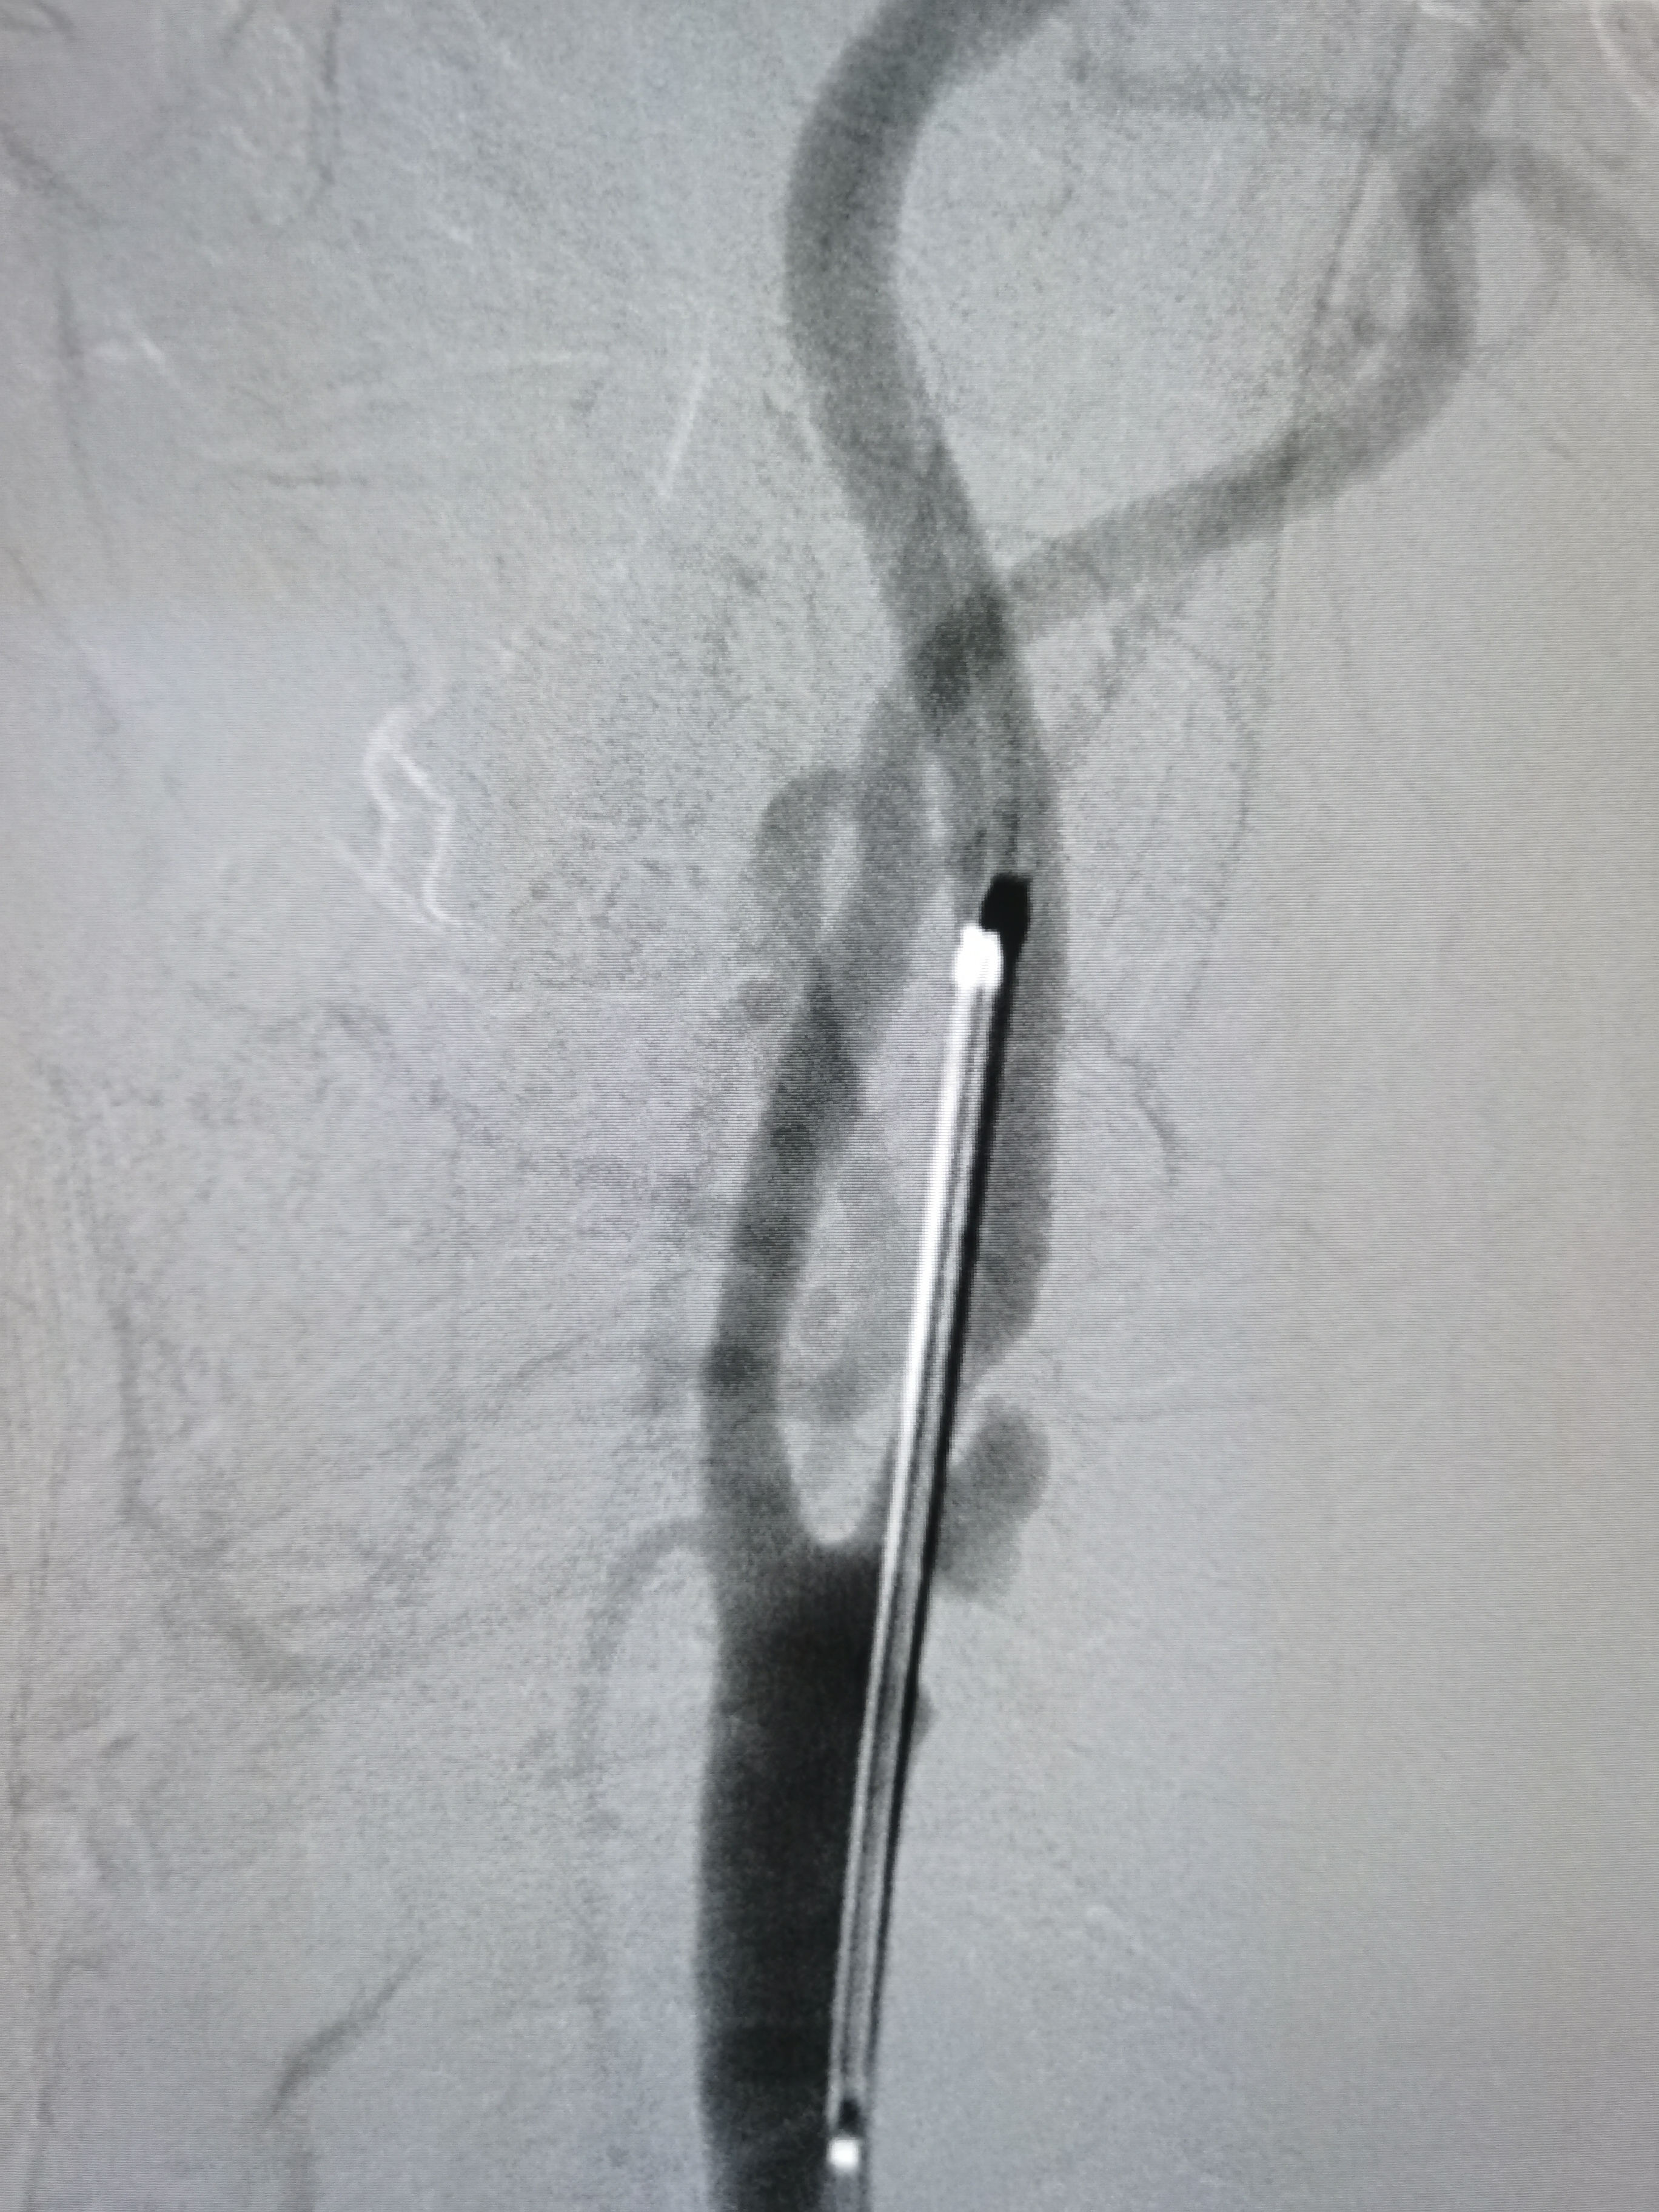

微导丝顺利通过病变,交换入远端保护伞。

2/20,4/30球囊渐进性预扩后狭窄改善。

9/30支架定位后释放。

支架释放后狭窄解除。

将导引导管调至左侧颈总动脉末端,远端置入保护伞。

9/30支架定位。